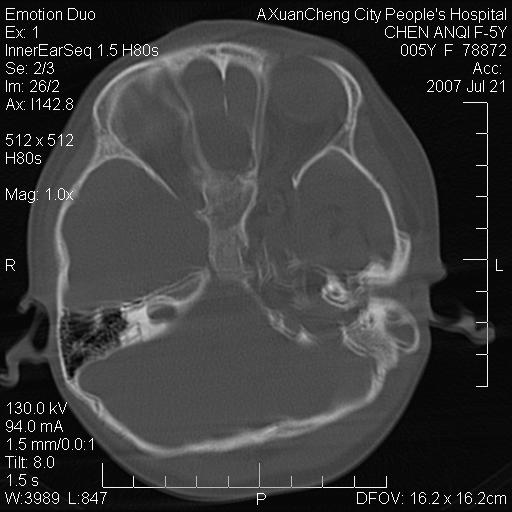

标题: PED0273:5岁,左耳流脓痛疼一周,颅底骨质破坏 [打印本页]

标题: PED0273:5岁,左耳流脓痛疼一周,颅底骨质破坏

患儿5岁,左耳流脓痛疼一周,左外耳道肉芽组织填塞 软组织窗显示病灶内结节状低密度影为气体密度

左侧中耳炎并胆脂瘤,左颞骨岩部骨质破坏并颅内感染积气。

考虑化脓性中耳乳突炎伴胆脂肪瘤形成并左颞叶感染,不除外合并嗜酸性肉芽肿.

考虑化脓性中耳乳突炎伴胆脂瘤形成合并左颞叶感染,不除外伴嗜酸性肉芽肿.